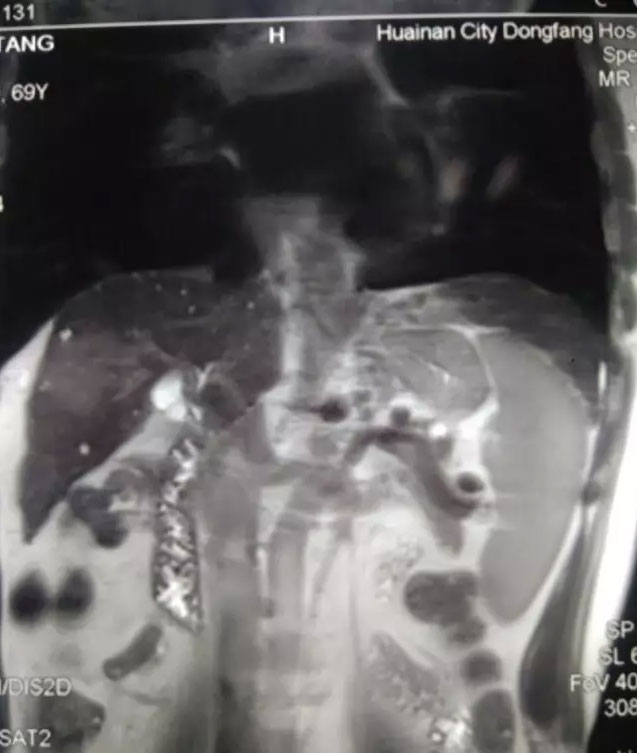

患者是一名老年男性,71岁,淮化集团退休职工,因体检发现肝脏右叶肿瘤来到总院就诊。该病人年事已高,合并乙肝肝硬化,体内肿瘤较大。在我市多家医院就诊后,均建议转上级医院治疗。可是,病人家庭经济困难,无力承担大城市高昂的治疗费用。左右为难之际,一家人抱着最后的一线希望,慕名来到东方医院肝胆胰外科。得知病人的病情后,徐友标和张军两位副主任热情接待,详细的了解和评估病情,做相关的医学检查,并及时向江永强副院长汇报。江院长随即组织医生组进行讨论,结论为:高龄患者,有乙肝病史多年,合并肝硬化,肝功能储备差,肝癌肿瘤大,位于肝脏V、Ⅷ段,临近肝中静脉,与门静脉右支和胆囊关系密切,手术难度较大,围手术期风险并发症发生率高。尤其患者几经折腾,信心丧失,对传统开放手术,产生不信任和恐惧抵触情绪。

根据实际情况,江院长查阅目前国内外先进的肝脏肿瘤治疗新术式和大量资料文献,决定引进国内一流的完全腹腔镜下解剖性右半肝切除(大概需要切除55%的病变肝脏肿瘤组织)。为了确保手术安全性和成功率,邀请了上海复旦大学附属中山医院肝癌研究所专家高强教授前来指导,高强教授有着五百多例腹腔镜肝肿瘤切除经验和两百多例肝移植经验,是国内一流的微创手术专家,在他的指导下,徐友标、张军两位副主任娴熟配合,手术顺利开展。术后,高强教授认为总院外科两位主任的手术技巧如行云流水般一气呵成,并对总院先进精良的腹腔镜设备给予高度肯定和赞扬。手术历时约210分钟,出血量微小。